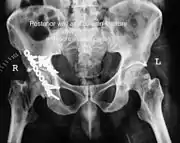

Posterior wall fracture fixed with screws and plate

Posterior column and wall fracture as seen on 3D CT

Posterior column and wall fixed using screws and plates